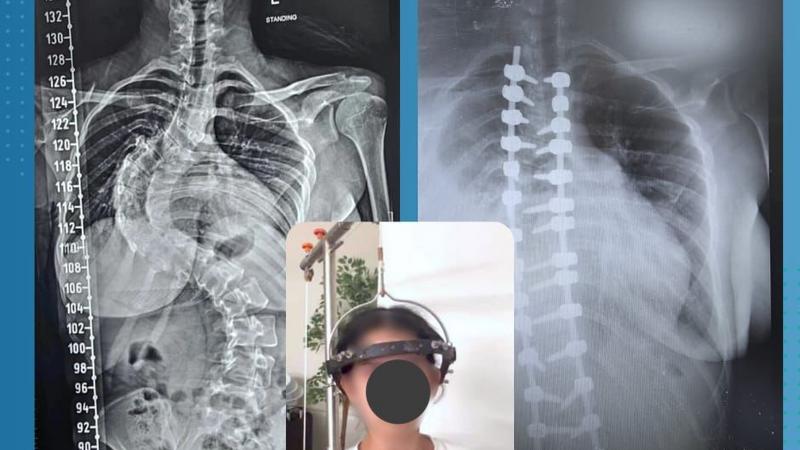

فريق طبي أردني يُجري تدخلًا جراحيًّا دقيقًا في العمود الفقري بمستشفى حمزة